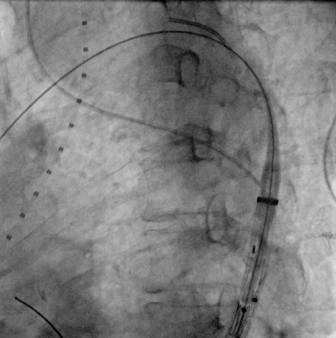

上推支架

主体释放

经DSA造影确认位置准确,快速释放支架主体,助手牵拉并释放分支支架,再行造影后确认,支架定位准确。

治疗车怎么推【弓部重建直通车】梅州市人民医院心内科团队运用Castor®分支型支架联合预开窗技术治疗主动脉弓动脉瘤合并迷走右锁骨下动_https://www.jmylbn.com_新闻资讯_第11张

释放支架